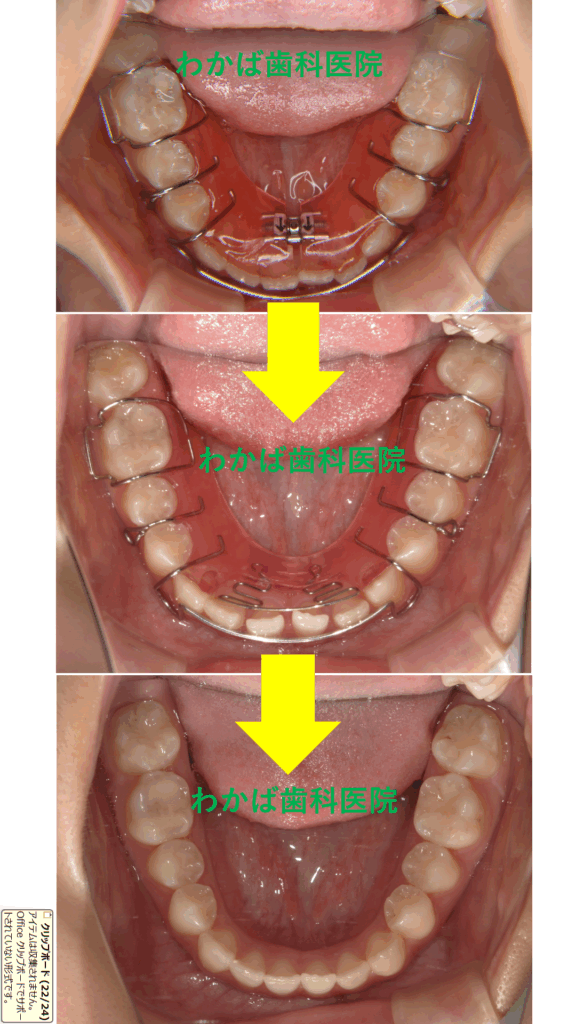

高校1年生の症例です🔍

小学5年生から矯正をスタートしました❣️

上下とも拡大床1個+下サンド1個+上ブラケット装着+リテーナーを使用しました。